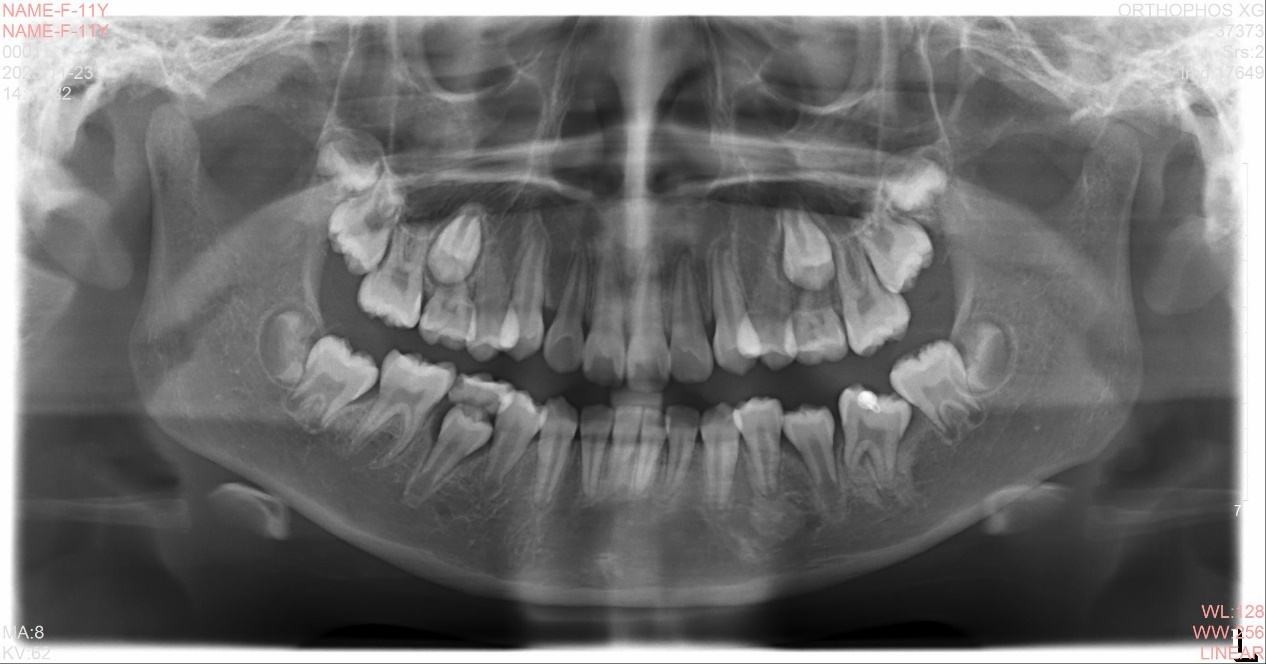

当女孩来我院就诊时,医生拍片发现36含牙囊肿,低位埋伏阻生,且牙根弯曲度大,根尖弯曲接近180°,牵引难度很大,但考虑患者才10岁,拔除非常可惜。

经过对病例的全面分析,决定为其设计数字化3D打印个性化矫治器,尝试进行36牵引,通过数字化口内扫描,结合CBCT进行精准定位,制作出3D打印牵引装置。该方法可以在替牙晚期,多数乳磨牙出现松动的情况下,充分增加固位,且舒适度高。经过大半年的时间,36通过牵引,口内大部分萌出,成功为患儿保留了一颗重要的牙齿。患儿及家长非常开心,安心等待替牙完成后进行全口矫正。